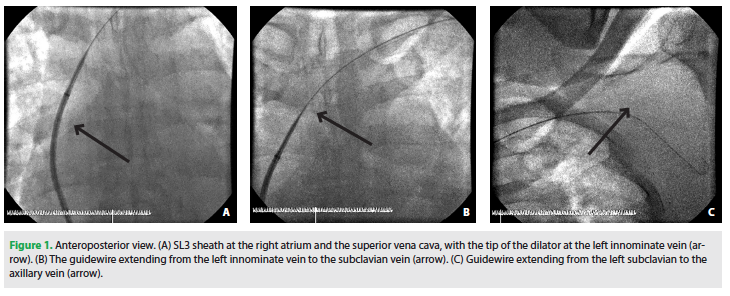

benefits, procedure length, anesthesia requirement, lead and device placement, postoperative observation, pain management, and follow-up care. The procedures were conducted in a well-equipped and adequately sterilized operating suite. Adequate conscious sedation facilitated patient comfort. As a preparation of target vein selection, we routinely perform occlusive venography to the coronary sinus (CS) using an SL3 sheath and attain the balloon via the right femoral vein. A 0.035 mm guidewire is then introduced retrogradely from the femoral vein up to the left axillary vein, passing through the inferior vena cava, right atrium, superior vena cava, left innominate vein, and left subclavian vein, supported by the SL3 sheath and its dilator. While the guidewire is in the vein, an anteroposterior (AP) scene at 7.5 frames/second is captured. The scene is then retained as a roadmap for axillary vein puncture using AP view during the implantation procedure. An SL3 sheath as well as the guidewire are then pulled back into the right atrium, in which the wire and dilator are exchanged with the attain balloon to cannulate the CS in order to perform the occlusive venography. Axillary vein punctures were attempted after device pocket preparation. Time to successful puncture was recorded. The procedure is then completed as per the protocol. Blood pressure, pulse, temperature, and pulse oximetry are monitored throughout the procedure.